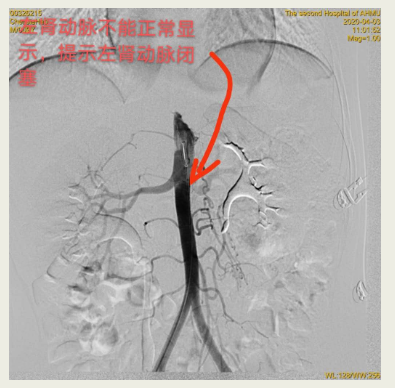

“入院时发现患儿血压异常增高,最高血压达到190/160mmHg。”接诊乐乐的安医大二附院儿科主任项云介绍说,由于反复头疼、呕吐,来到医院时患儿已经不能进食。项云表示,如此高血压,在儿童中间十分少见。即使是成年人,血压如此之高,也已经达到重度高血压的标准。对于这样一位特殊的小患者,安医大二附院儿科、放射科、超声诊断科、介入科等多学科齐上阵,反复多次进行会诊,决定对患儿进行相关检查。经过CT血管成像及DSA血管造影检查,医生发现乐乐左侧肾动脉闭塞,左肾萎缩明显。于是,儿科与该院泌尿外科、血管外科再次进行会诊并确定了手术方案。4月9日,在多学科密切配合下,由血管外科、泌尿外科团队为乐乐进行左侧肾动脉血管成形术,手术顺利地为闭塞的左肾动脉打开了一条正常的通道。